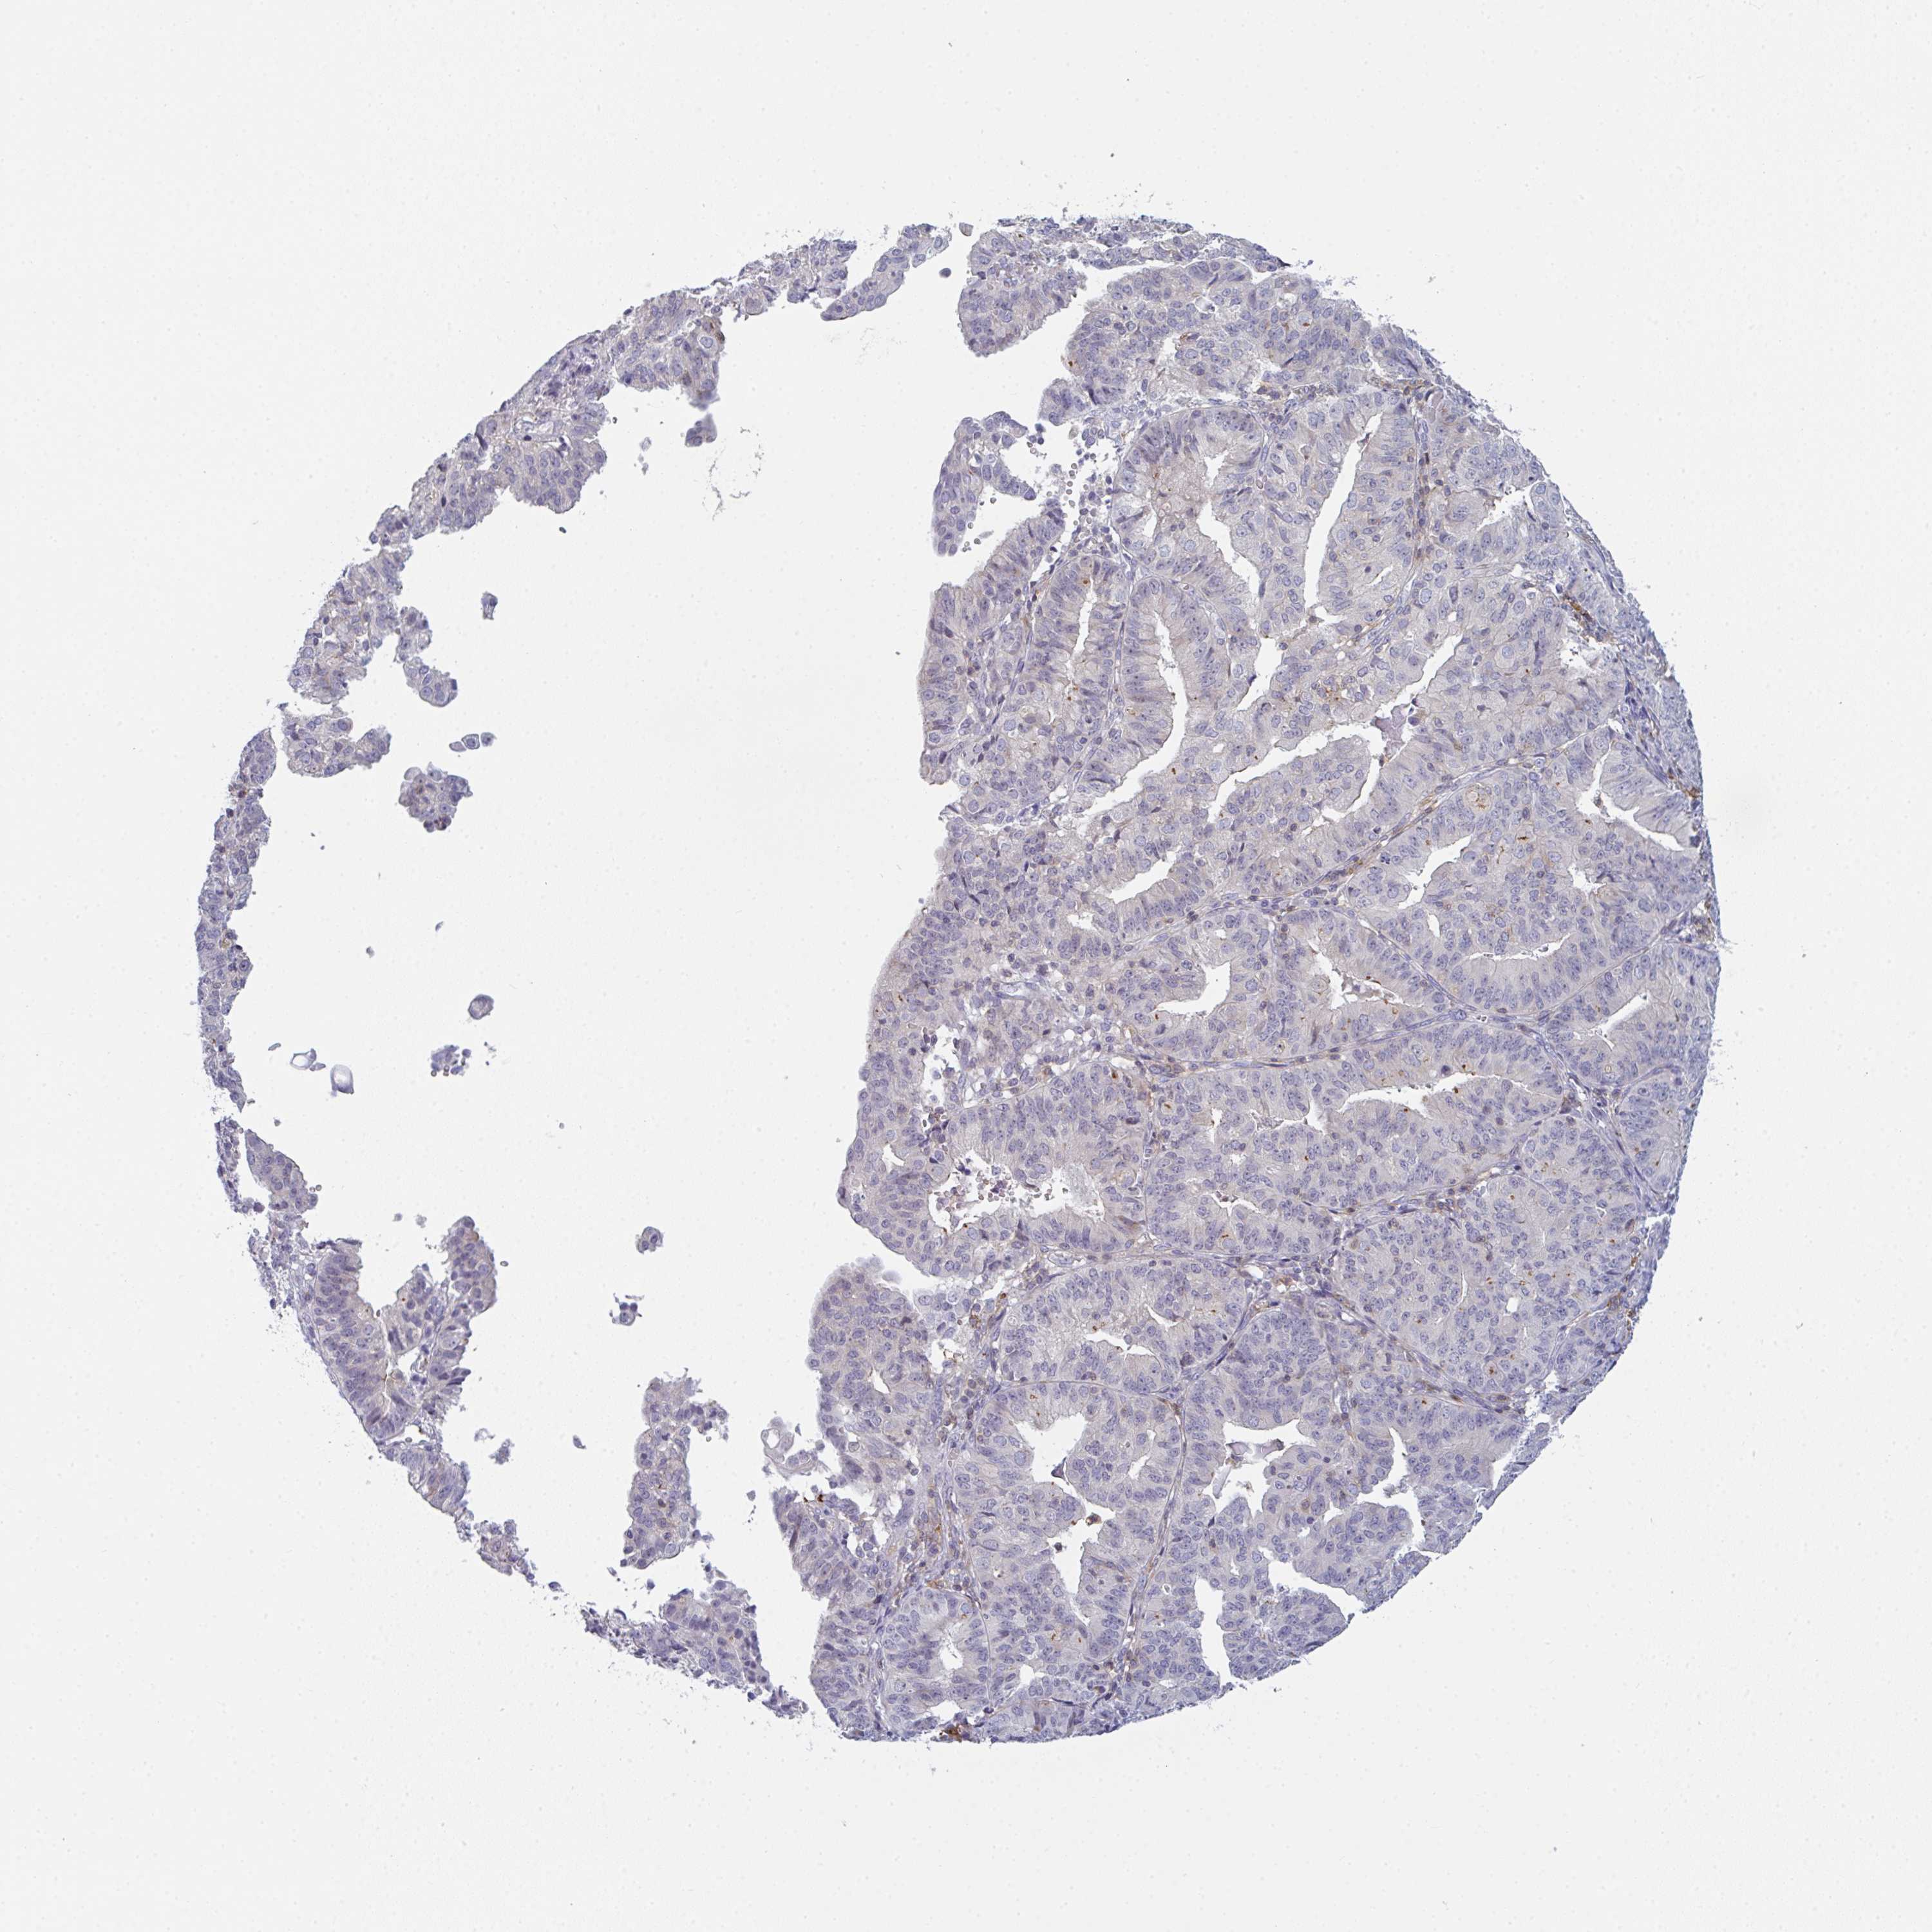

ENDOMETRIAL CANCER - Protein expressioni

A mouse-over function shows sample information and annotation data. Click on an image to view it in a full screen mode. Samples can be filtered based on level of antibody staining by selecting one or several of the following categories: high, medium, low and not detected. The assay and annotation is described here.

Note that samples used for immunohistochemistry by the Human Protein Atlas do not correspond to samples in the TCGA dataset.

Antibody stainingi

Antibody staining in the annotated cell types in the current human tissue is reported as not detected, low, medium, or high, based on conventional immunohistochemistry profiling in selected tissues. This score is based on the combination of the staining intensity and fraction of stained cells.

Each image is clickable and will lead to virtual microscopy that enables deeper exploration of all samples and also displays staining intensity scores, fraction scores and subcellular localization as well as patient and tissue information for each sample.

Antibody HPA050092

Antibody CAB025368

Staining

High

Medium

Low

Not detected

Intensity

Strong

Moderate

Weak

Negative

Quantity

>75%

75%-25%

<25%

None

Location

Nuclear

Cytoplasmic/membranous

Cytoplasmic/membranous,nuclear

Adenocarcinoma, NOS

Carcinoma, NOS

Adenocarcinoma, metastatic, NOS